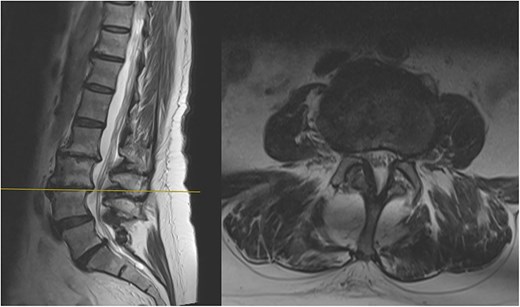

The MRI report detailed the vertebral bodies, discs, and spinal cord but did not comment on the surrounding spinal musculature. On review of the images, no clear impingement of the spinal nerves was seen (Fig. 2). It was, however, noted that there was significant fat infiltration of the paraspinal muscles (Fig. 3).

Sagittal and axial section at L3/4 showing no significant spinal stenosis or nerve root impingement.